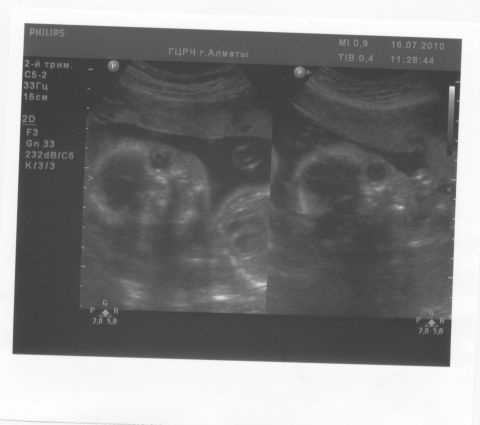

Еще вот наши мордашки на сроке 23 недельки

Не всем, но многим видно глазки, ручки… У нас до сих пор это фото дикий восторг вызывает!

Да, первое портретное фото наших девочек, правда непонятно где кто)))